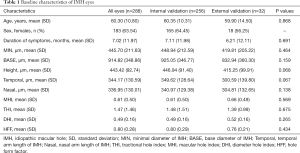

The demographics of the eyes are summarized in Table 1. Among 288 eyes, 183 were from female patients (63.54%). The mean age was 60.30±10.80 years, and the mean duration of symptoms was 7.02±11.97 months. There were 208 eyes with a closed IMH (72.22%) and 80 eyes with an open IMH (27.78%) after VILMP surgery, as we intentionally included more IMH-open eyes to statistically balance the cases regardless of the real-world incidence. For the reproducibility of OCT measurements, the inter-observer ICC was 0.958 for MIN, 0.847 for BASE, 0.910 for H, 0.923 for T, and 0.933 for N, suggesting good reproducibility between the two retinal specialists (X.Z., Y.X.). There was no significant difference in each baseline parameter between the internal validation set and external validation set, suggesting small selection bias and good homogeneity of the two datasets.

Full table